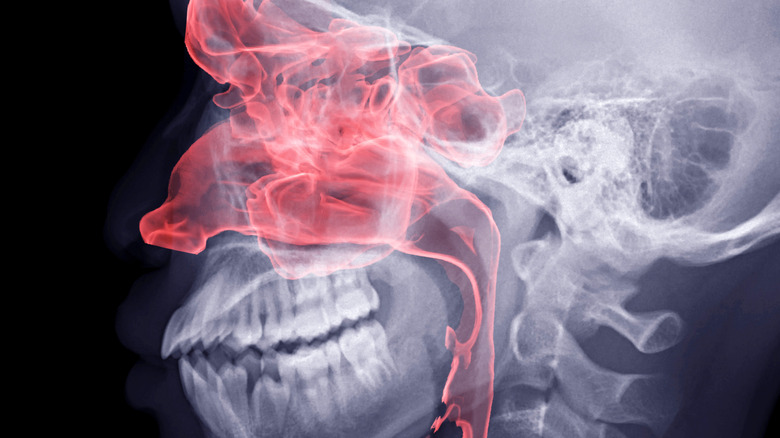

Le débat sur la question de savoir si les humains possèdent ou non un VNO est réglé. Les dissections, les IRM, les tomodensitogrammes, les endoscopies et même la microscopie électronique ont tous confirmé son existence chez l’homme. Il se trouve à l’intérieur de notre nez, près de l’arête nasale, là où le cartilage rencontre les os. Les anatomistes le décrivent comme un « sac aveugle », ce qui signifie que ses cellules sensorielles fonctionnent de la même manière que le reste de notre système olfactif ; Lorsque l’air inspiré par le nez passe sur le VNO, des cellules sensorielles spécialisées prélèvent des « échantillons » pour détecter les produits chimiques en suspension dans l’air et alerter le cerveau de leurs caractéristiques. La question de savoir si ces cellules sensorielles spécialisées du VNO peuvent ou non distinguer des phéromones spécifiques reste cependant un sujet de débat.